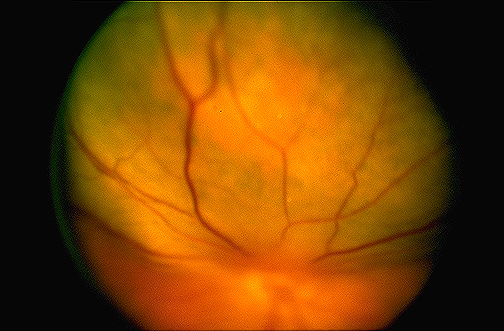

| The discoloration and bulging underlying the retina shown here are the result of an intraocular melanoma. The melanoma usually arises in the pigmented choroidal layer. Melanoma is the most common intraocular neoplasm of adulthood. [Image contributed by Nick Mamalis, MD, University of Utah] |